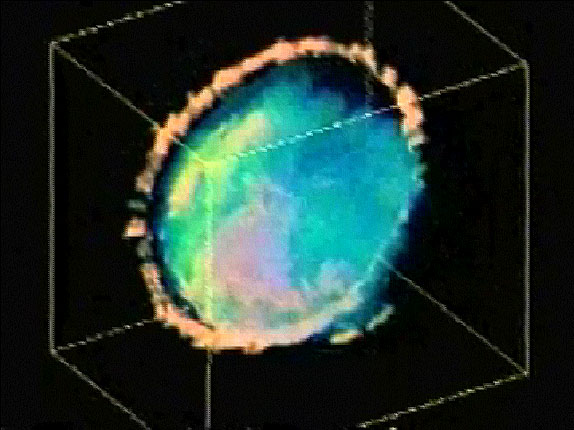

ana.words, scheimlinse

scheim scheimlinse mit scheimpflug Here, a three-dimensional recording of a human lens is made using a microscope called a Scheimpflug…